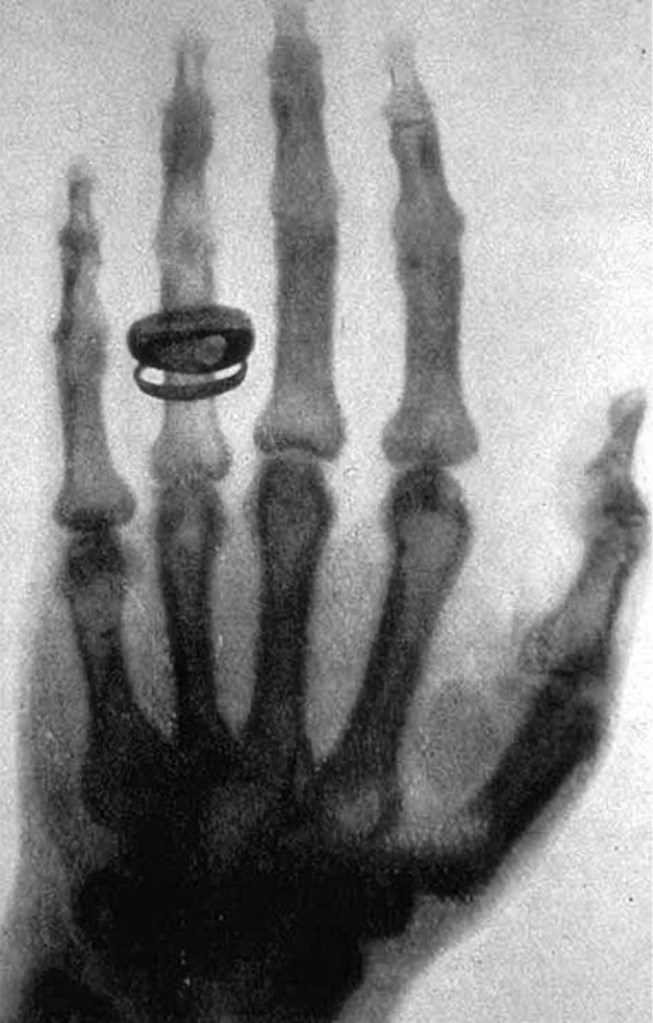

Roentgen’s legacy is truly remarkable, stretching across disciplines, generations and geographical boundaries. The fact that we are discussing his legacy on Café Roentgen, a platform named in his honour, is a testament to the enduring impact of his work. The logo of Café Roentgen features a hand radiograph (complete with the ring), holding a radiopaque cup with “Café Roentgen” written on it in a font reminiscent of the film The Godfather. It is therefore appropriate that we first talk about the (God)father of radiology, and two hand radiographs (with rings) that he famously captured.

On the fateful afternoon of 8 November 1895, Roentgen connected the Crookes-Hittorf tube to a pair of electrodes and dimmed the room. To his astonishment, he observed a faint shimmering image of a nearby bench each time he discharged the tube. Further experiments over the weekend confirmed his suspicion of a new type of rays. Naming them “X-rays” (with “X” representing the unknown), Roentgen dedicated himself to their study, and in this process captured the first radiographic image — a flickering silhouette of his own skeleton, an image that is unfortunately lost. Around six weeks after his groundbreaking discovery, Roentgen captured another radiograph – this time of the hand of his wife, Anna Bertha. When she saw the silhouette of the skeleton of her hand, she remarked, “I have seen my own death.”

Anna’s hand radiograph, a part of Roentgen’s personal collection, is truly iconic, to say the least. It’s a fuzzy image that shows the bones of her hand, and the ring that adorns it. Countless radiology professionals have seen this image, making it perhaps the most defining emblem of the field. This radiograph marks a seminal moment in medical history, and Anna’s contribution to the world of radiology remains invaluable.

But there is another radiograph captured by Roentgen that is often confused with this one, and that too has an interesting story associated with it.

On 23 January 1896, he was in the audience for a lecture by Roentgen on his recent discovery, who had been invited by the Physical-Medical Society of Würzburg for a talk. This would be the only public lecture that Roentgen would ever take on X-rays. During the lecture, Roentgen called von Kölliker to the stage as a volunteer and captured a radiograph of his hand. Amazed by what he saw, von Kölliker suggested the unknown rays be called “Roentgen Rays”. The audience agreed in a standing ovation.

Roentgen’s radiograph of von Kölliker’s hand marked a significant advancement in the nascent field of radiography. This image represented a refinement compared to the earlier radiograph of Anna’s hand. In the weeks following his discovery, Roentgen diligently refined and fine-tuned the technical aspects of the imaging process. His meticulous adjustments led to significantly enhanced clarity, allowing him to capture the more intricate details of the anatomy of von Kölliker’s hand. This showcased the potential of X-ray technology for medical diagnostics, highlighting specific bone structures and nuances previously invisible to the human eye. The radiograph of von Kölliker’s hand not only demonstrated Roentgen’s mastery of the X-ray technique but also demonstrated the scope for future advancements in the field of medical imaging.